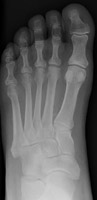

Freiberg's Infarction

This is a form of avascular necrosis. It is idiopathic (possibly post-traumatic). The process typically affects the second metatarsal head and is unilateral.

- Click on the image for a larger versionAAP radiograph of the foot. The typical appearance of Freiberg's infarction.